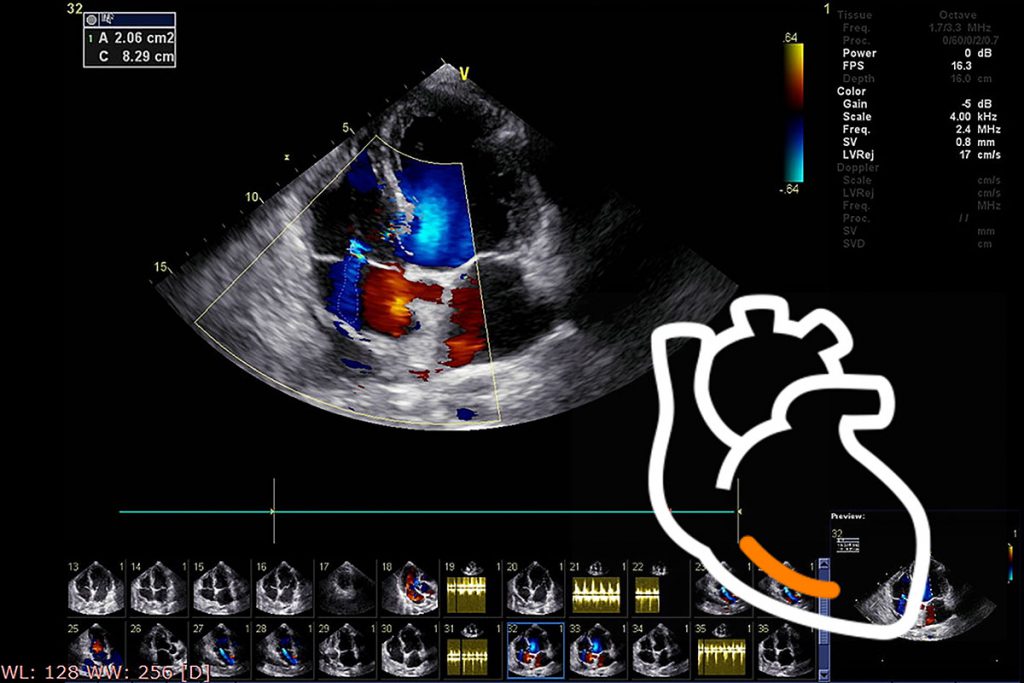

血管年齢・頸部エコー・動脈硬化について | 名古屋市昭和区 横山, ストップ!動脈硬化「危険を予測 最新検査」 - きょうの健康 - NHK,

ストップ!動脈硬化「危険を予測 最新検査」 - きょうの健康 - NHK, 循環器検査 | 名古屋循環器科・内科 | 中村区名駅,

循環器検査 | 名古屋循環器科・内科 | 中村区名駅, 頸動脈エコーと動脈硬化検査 | 川崎市幸区の川崎中央クリニック,

下肢血管病の診断・治療 | 青山クリニック, 四谷三丁目・四谷・四ツ谷の内科・循環器内科・外科 | まがり,

四谷三丁目・四谷・四ツ谷の内科・循環器内科・外科 | まがり, 心臓・血管の専門検査 - 名古屋市名東区 内科 循環器内科 皮膚科,

心臓・血管の専門検査 - 名古屋市名東区 内科 循環器内科 皮膚科, 血管エコーの最新動向 - 新。超音波診断 Vol.03 - 東芝,